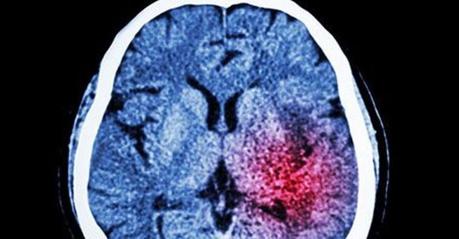

En la última semana la Sociedad Española de Neurología ha aportado una serie de datos relativos al ictus, una enfermedad cada vez más habitual entre la población a nivel global.

Se estima que el 17% de las personas la sufrirá a lo largo de su vida, la mitad de las cuales padecerá secuelas de carácter grave, o fallecerá.

En términos absolutos, cada año en España sufren un ictus 120.000 personas. Actualmente es la segunda causa de muerte a nivel nacional. No obstante, este trastorno sigue siendo un gran desconocido entre la población. La gran mayoría de personas no conoce cuáles son sus síntomas y, además, cree que afecta única y exclusivamente a personas ancianas.